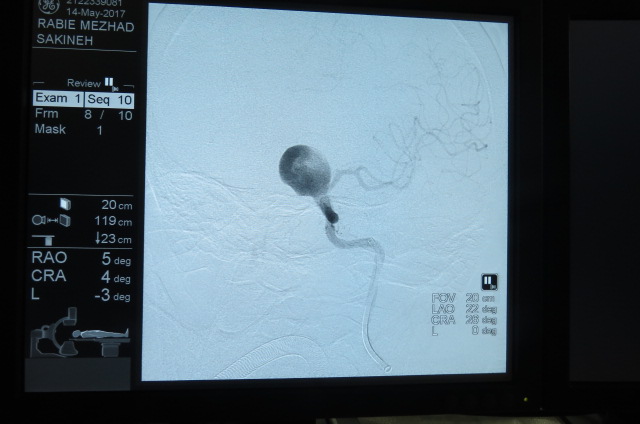

بیمار خانم 63 ساله می باشد به علت سرگیجه به بیمارستان مراجعه کرده است ، در MRI ضایعه بزرگ به اندازه 25MM گرد شبیه تومور مشاهده شده که در آنژیوگرافی مغزی ضایعه آنوریسم مغزی تشخیص داده شد،بیمار توسط تیم جراحی به سرپرستی دکتر کهنسال تحت جراحی بسته ( اینترونشن ) مغزی قرارگرفت و آنوریسم مغزی کاملا بسته شد و بیمار به بخش منتقل شد .